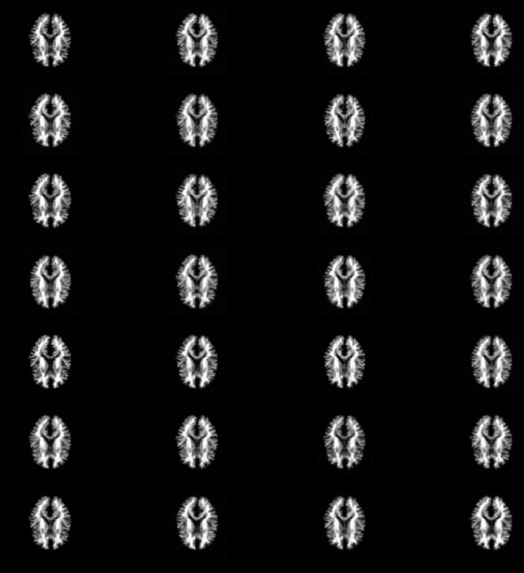

One of the main aspects of our project is MRI Image Synthesis. In this, we convert T1-Weighted images into T2-Weighted images. Along with this, our other model helps by generating Segmented Brain MRI images to show the distribution of white matter.

So we have created two models, one for Image synthesis and the other does Segmentation. Both works on generating images. We have implemented VAEs to achieve the purpose.